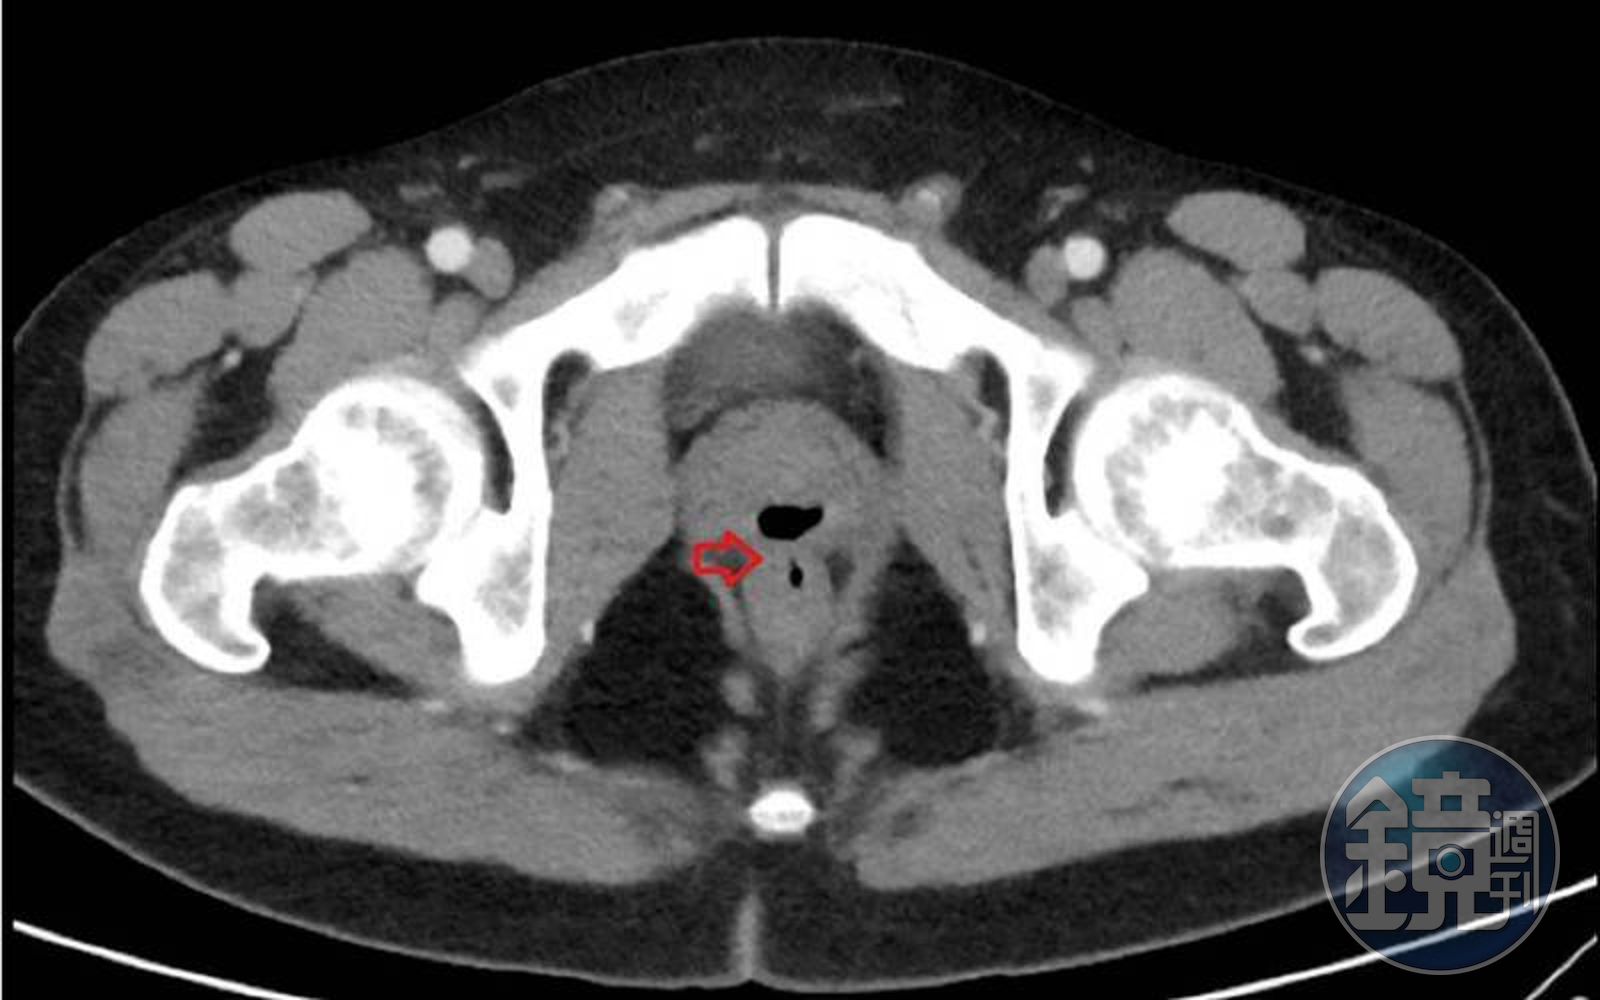

透過CT報告也可見,男子的直腸與尿道之間有一稱為「瘻管」(Fistula)的異常管道,因內部充滿空氣,導致尿道產生了大量氣體,隨著尿液一起排出,就如同放屁一樣,這種症狀則被稱為「氣尿症」(Pneumaturia),日前男子的前列腺和直腸經手術後,留下了一條「隧道」供氣體正常排放,並透過服藥治療發炎、腫脹的睪丸。